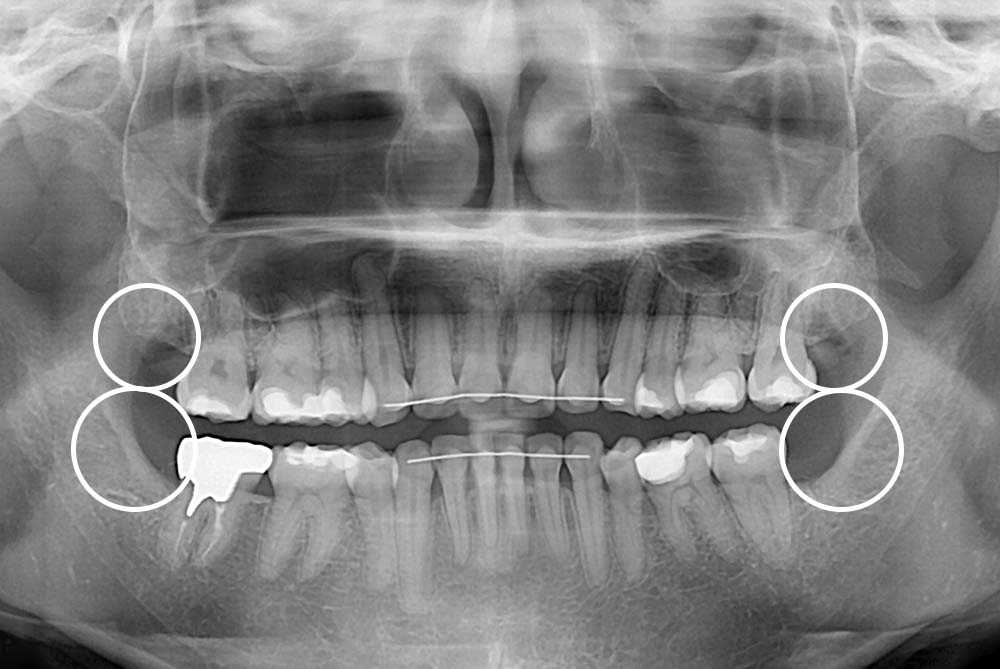

[사랑니] 매복 사랑니 발치

치료전 : 2019-03-27